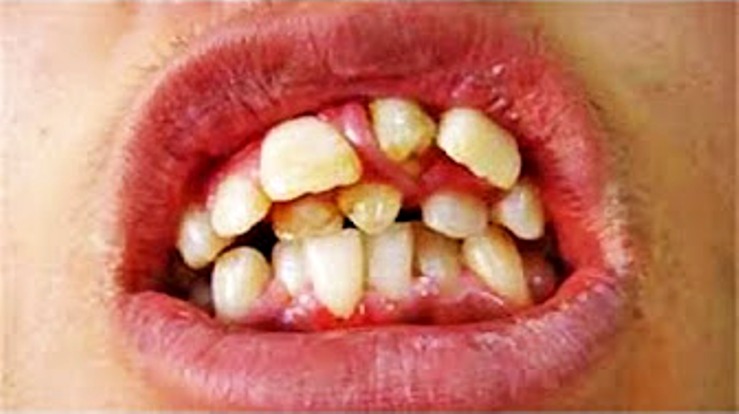

Hyperdontia: the presence of extra (supernumerary) teeth.

Below are examples of mild cases, and examples of extreme cases.

EXTREME CASES

Hyperdontia is the condition of having supernumerary teeth, or teeth that appear in addition to the regular number of teeth. They can appear in any area of the dental arch and can affect any dental organ.

There is evidence of hereditary factors along with some evidence of environmental factors leading to this condition. While a single excess tooth is relatively common, multiple hyperdontia is rare in people with no other associated diseases or syndromes. Many supernumerary teeth never erupt, but they may delay eruption of nearby teeth or cause other dental or orthodontic problems. Molar-type extra teeth are the rarest form. Dental x-rays are often used to diagnose hyperdontia.

It is suggested that supernumerary teeth develop from a third tooth bud arising from the dental lamina near the regular tooth bud or possibly from splitting the regular tooth bud itself. Supernumerary teeth in deciduous (baby) teeth are less common than in permanent teeth.

Supernumerary teeth can be classified by shape and by position. The shapes include the following:

• Supplemental (where the tooth has a normal shape for the teeth in that series);

• Tuberculate (also called barrel shaped);

• Conical (also called peg shaped);

• Compound odontoma (multiple small tooth-like forms);

• Complex odontoma (a disorganized mass of dental tissue)